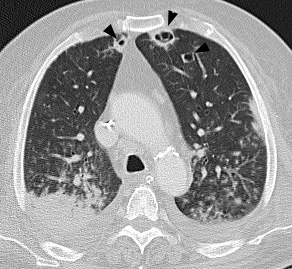

Paciente masculino de 70 años de edad con EPS asociada a artritis de cadera derecha por Staphylococcus aureus meticilino-resistente.La embolia pulmonar séptica (EPS) se define como la presencia de trombos sépticos en la circulación pulmonar provenientes de un foco infeccioso extrapulmonar. La obstrucción del flujo en vasos de pequeño calibre (secundaria a la presencia de émbolos infecciosos en la luz del vaso), puede condicionar el desarrollo de infartos y abscesos pulmonares.Las entidades asociadas a EPS son de naturaleza variada e incluyen: infecciones asociadas a dispositivos intravasculares, endocarditis infecciosa, abscesos hepáticos, infecciones en piel y tejidos blandos, tromboflebitis séptica, síndrome de Lemierre e infección periodontal. Los microorganismos aislados con mayor frecuencia son: cocos gram positivos (Staphylococcus aureus, Staphylococcus coagulasa negativo, Streptococcus spp.) y bacilos gram negativos (Fusobacterium, Klebsiella pneumoniae).Las manifestaciones clínicas de EPS son inespecíficas (fiebre, disnea, tos, dolor torácico pleurítico y hemoptisis).Las alteraciones en los estudios de imágenes son esenciales en el diagnóstico de EPS.En la radiografía de tórax de pacientes con EPS se describen opacidades nodulares, consolidación, lesiones cavitadas y derrame pleural.La tomografía computarizada (TC) es la imagen de mayor utilidad en la valoración de pacientes con sospecha de EPS. Las manifestaciones de EPS en TC se describen en la Tabla 1.